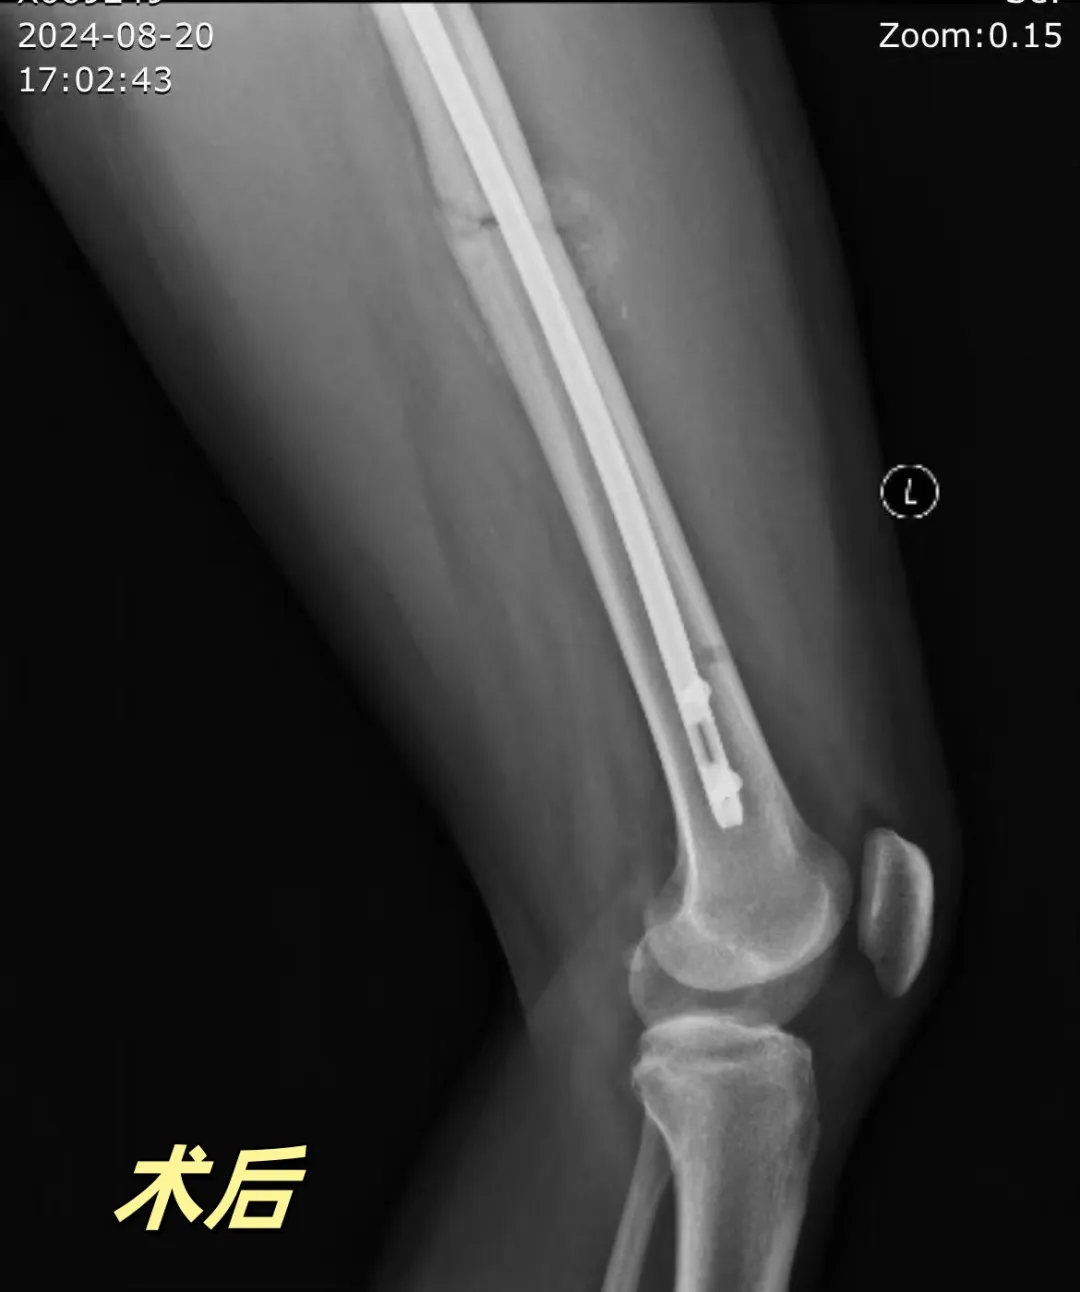

案例1

前不久“小明同学”骑电动车不慎摔伤左大腿,到威海卫人民医院关节外科门诊检查诊断为“左股骨中段骨折”,并予以初步固定,缓解患者疼痛。经过详细的检查和评估,专家团队决定为小明同学实施股骨髓内钉手术。手术由毕前航主任亲自主刀,凭借精湛的技术、丰富的髓内钉固定经验,团队默契配合精准地将髓内钉植入骨髓腔中,对骨折部位进行内固定。整个手术过程仅耗时一个多小时,出血量少,创伤小。

术后,关节外科制定了个性化的康复计划,包括物理治疗、功能锻炼和心理疏导等。小明同学在关节外科医护人员的精心护理下,骨折部位愈合良好,功能逐渐恢复,回到了正常的生活和学业轨道。